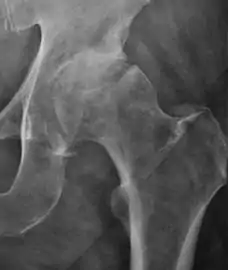

Projectional radiography ("X-ray") is the first imaging technique of choice in hip pain, not only in older people with suspected osteoarthritis but also in young people without any such suspicion. In this case plain radiography allows categorization as normal hip or dysplastic hip, or with impingement signs, pincer, cam, or a combination of both.[1]

Projectional radiography ("X-ray") is currently useful not only in older people in whom osteoarthritis of the hip is suspected but also in younger people without osteoarthritis, who are being evaluated for femoroacetabular impingement (FAI) or hip dysplasia.[1]

Plain radiography allows us to categorize the hip as normal or dysplastic or with impingement signs (pincer, cam, or a combination of both). Besides these, pathologic processes like osteoarthritis, inflammatory diseases, infection, or tumors can also be identified (Figure 1).[1]

- Osteoarthritis

In adults, one of the main indications for radiographs is the detection of osteoarthritic changes (Figure 1(e)). Nevertheless, radiographs usually detect advanced osteoarthritis that can be graded according to the Tönnis classifications. The grading system ranges from 0 to 3, where 0 shows no sign of osteoarthritis. Intermediate grade 1 shows mild sclerosis of the head and acetabulum, slight joint space narrowing, and marginal osteophyte lipping. Grade 2 presents with small cysts in the femoral head or acetabulum, moderate joint space narrowing, and moderate loss of sphericity of the femoral head. Grade 3 is the severest form of osteoarthritis, which manifests as severe narrowing of the joint space, large subchondral cyst with productive bone changes that may lead to deformity of the bone components of the joint, while secondary osteoarthritis due to calcium pyrophosphate deposition can be diagnosed when calcification of hyaline cartilage and fibrocartilage is detected.[1]

There are other pathological conditions that can affect the hip joint and radiographs help to make the appropriate diagnosis. Acute bacterial septic arthritis can be diagnosed by radiographs when a fast regional osteoporosis and destructive monoarticular process develops (Figure 1(f)). In case of tuberculous or brucella arthritis it is manifested as a slow progressive process, and diagnosis may be delayed.[1]